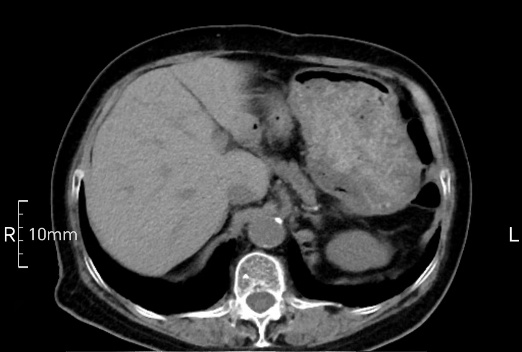

看看下面三幅便知遵醫(yī)囑的重要性。

沒禁食,胃內全是食物,導致胃壁顯示不清。